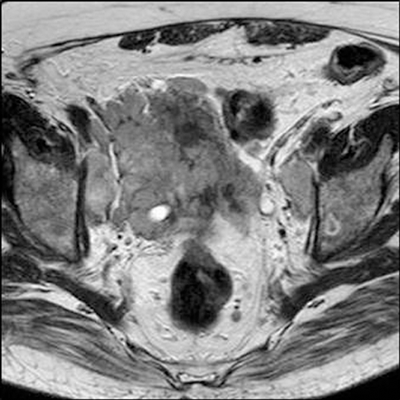

T4 disease is spread of tumour into adjacent tissues other than seminal vesicles, such as bladder, rectum or pelvic side-wall. Invasion is demonstrated by loss of the fat plane between the tumour and the structure, or in cases of more aggressive disease, visualisation of tumour within that structure (Figure 7) [3]. The sagittal T2W sequence is particularly useful at identifying bladder and rectal invasion [4].

Figure 7: Axial T2 showing extensive prostate tumour invading the bladder and bilateral iliac lymph nodes.

Large FOV axial T1W images are most useful for identifying local adenopathy. Criteria similar to those used in CT staging are often applied to MR to define clinically significant nodal involvement. Enlarged, spherical lymph nodes measuring at least 1cm in short axis dimension with loss of normal internal architecture are considered significant (Figure 7). Large FOV multiplanar T2W images of the abdomen and pelvis may be acquired to look for distant nodal disease or distant organ involvement. This is used in conjunction with CT, particularly in stage III or IV disease and when considering pre-treatment lymph node sampling [7]. T1 images should be evaluated to assess for bone metastases and will be seen as low signal intensity compared with the normal high signal marrow fat.